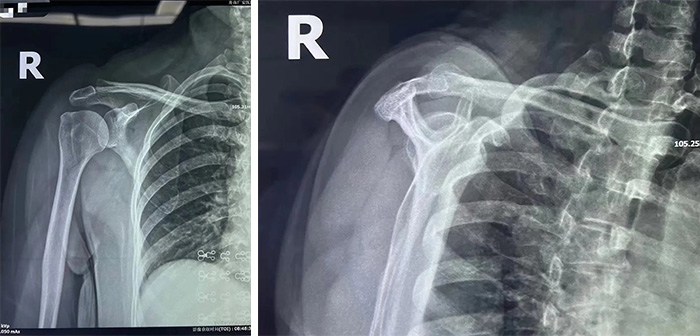

王女士的拍片顯示